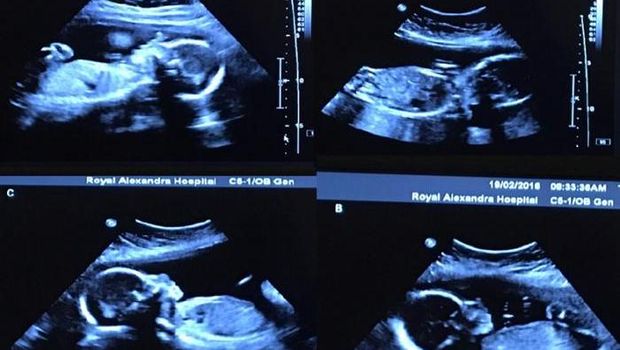

Hasil USG keempat bayi Tim dan Bethani Webb (Foto: Facebook) |

Hasil USG keempat bayi Tim dan Bethani Webb (Foto: Facebook)